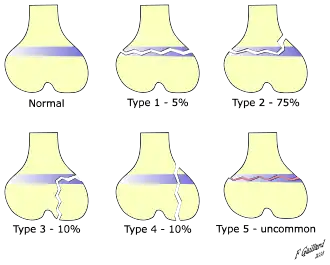

There are nine types of Salter–Harris fractures; types I to V as described by Robert B. Salter and William H. Harris in 1963,[3] and the rarer types VI to IX which have been added subsequently:[5]

- Type I – transverse fracture through the growth plate (also referred to as the "physis"):[6] 6% incidence

- Type II – A fracture through the growth plate and the metaphysis, sparing the epiphysis:[7] 75% incidence, takes approximately 12-90 weeks or more in the spine to heal.[8]

- Type III – A fracture through growth plate and epiphysis, sparing the metaphysis:[9] 8% incidence

- Type IV – A fracture through all three elements of the bone, the growth plate, metaphysis, and epiphysis:[10] 10% incidence

- Type V – A compression fracture of the growth plate (resulting in a decrease in the perceived space between the epiphysis and metaphysis on x-ray):[11] 1% incidence